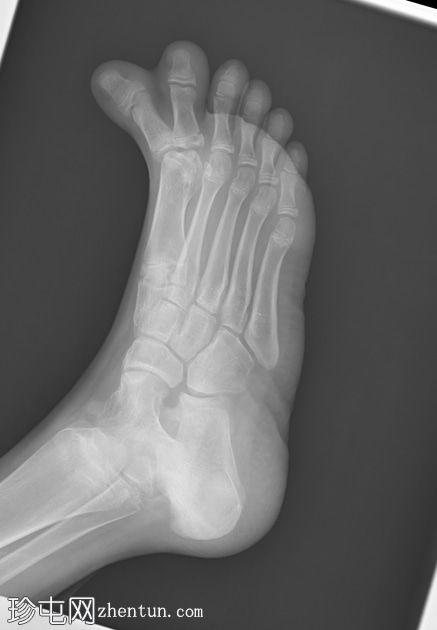

术前

X线片

正位片

侧位片

可见第一趾重复畸形,以第一跖骨为中心,多出的趾位于内侧并呈一定角度,同时伴有第一跖骨增宽。未见其他部位重复畸形。其他可见的骨骼和关节均正常。